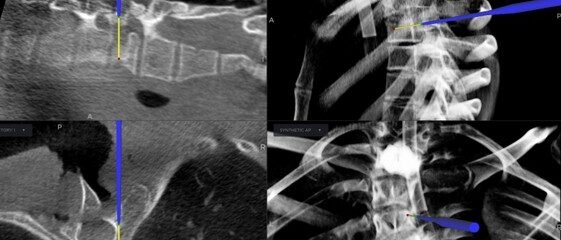

Receive a thorough assessment and personalized treatment plan including history taking, physical examination and relevant investigations to address your spinal issues effectively and empathetically.

Personalised pain management with oral, topical and injection medications, trigger point injections, advanced spinal injections (pars, foraminal, facet, annuloplasty, nucleoplasty, percutaneous discectomy, medial branch block) and TENS therapy.

For complex conditions, we provide state-of-the-art surgical interventions including keyhole and robotic surgeries to restore function and improve quality of life, backed by our skilled surgeon’s expertise.